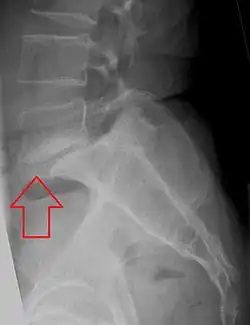

L5 S1 Spondylolisthesis Grade II with forward slipping of L5 on S1 <50%

Forward displacement of a proximal vertebra in relation to its adjacent vertebra in association with an intact neural arch, and in the presence of degenerative changes, is known as degenerative spondylolisthesis,[9][10] which narrows the spinal canal, and symptoms of spinal stenosis are common. Of these, neural claudication is most common. Any forward slipping of one vertebra on another can cause spinal stenosis by narrowing the canal. If this forward slipping narrows the canal sufficiently, and impinges on the contents of the spinal column, it is spinal stenosis by definition. If associated symptoms of narrowing exist, the diagnosis of spinal stenosis is confirmed. With increasing age, the occurrence of degenerative spondylolisthesis becomes more common. The most common spondylolisthesis occurs with slipping of L4 on L5. Frymoyer showed that spondylolisthesis with canal stenosis is more common in diabetic women who have undergone oophorectomy (removal of ovaries). The cause of symptoms in the legs can be difficult to determine. A peripheral neuropathy secondary to diabetes can have the same symptoms as spinal stenosis.[11]